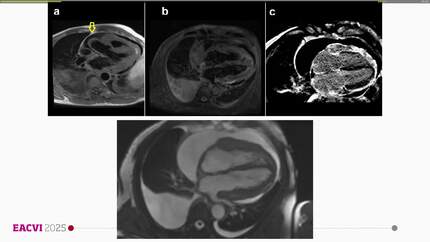

Unraveling constrictive physiology and coronary obstruction: a multimodality imaging guided diagnosis